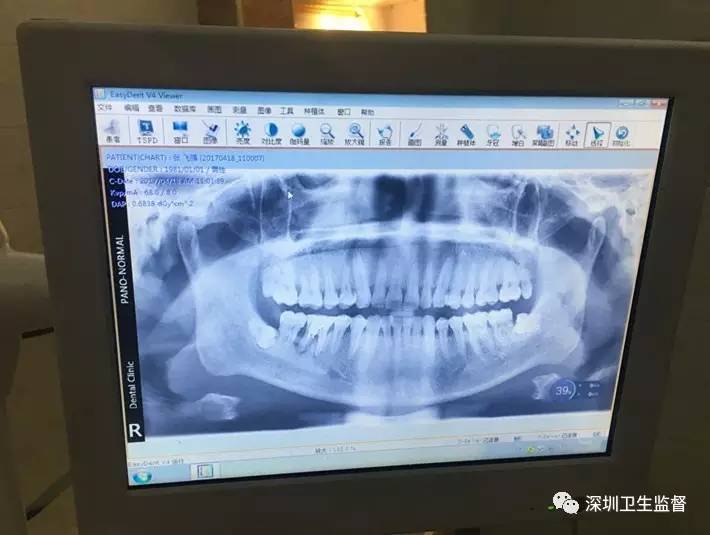

今年3月,龙岗区平湖街道一口腔门诊部为患者拍牙科全景片,开出了一张100元的收据......